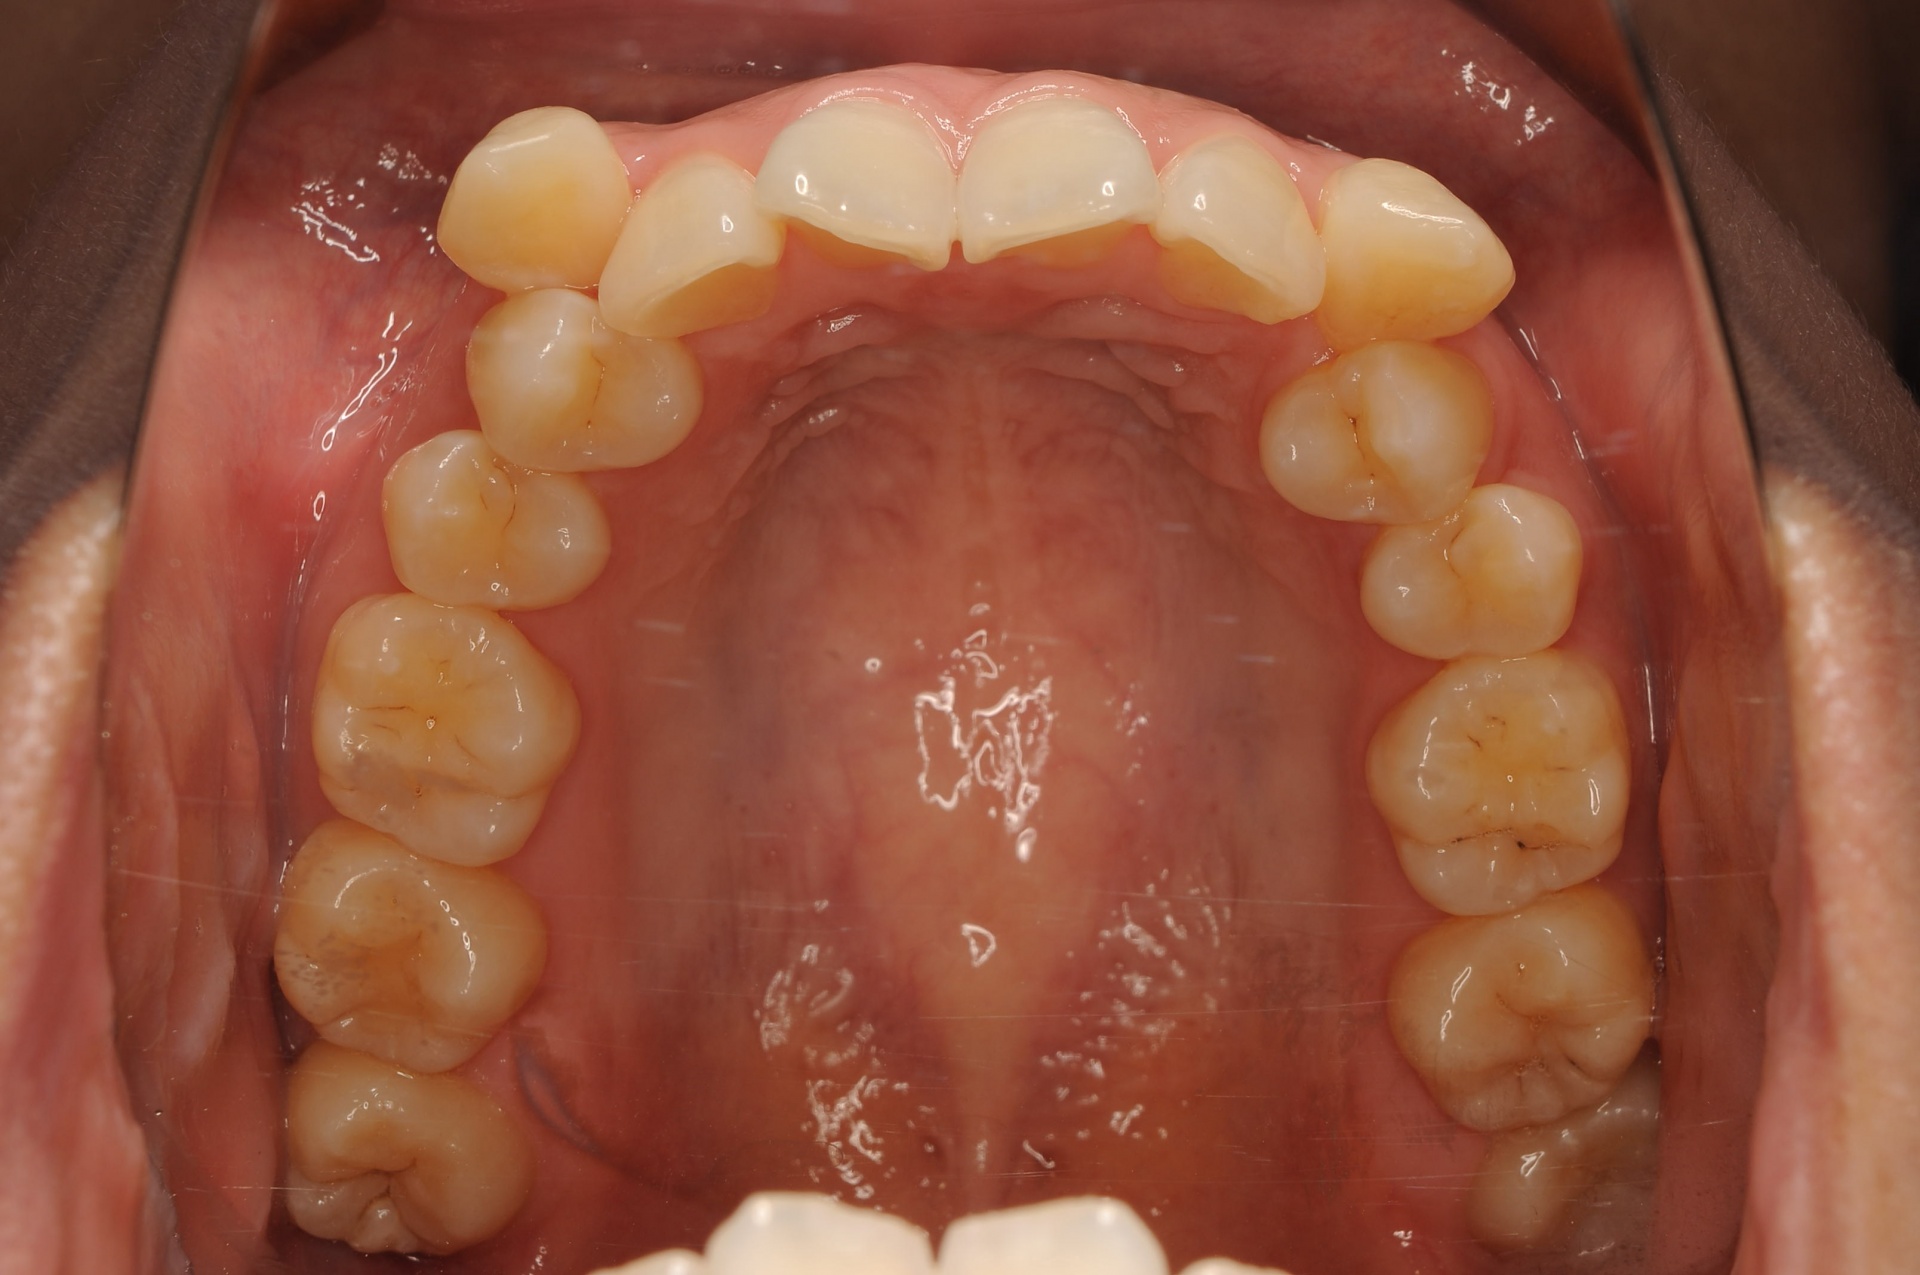

治療後

上下の正中は一致し、上顎両側犬歯は歯列内に誘導されました。奥歯の咬合関係は緊密で、再配列されたことにより機能・審美ともに改善されました。

| 治療内容 | 20代女性 上顎は叢生量が大きいため小臼歯抜歯のスペースを利用し、下顎は非抜歯で叢生を改善し各歯の再配列を行った |